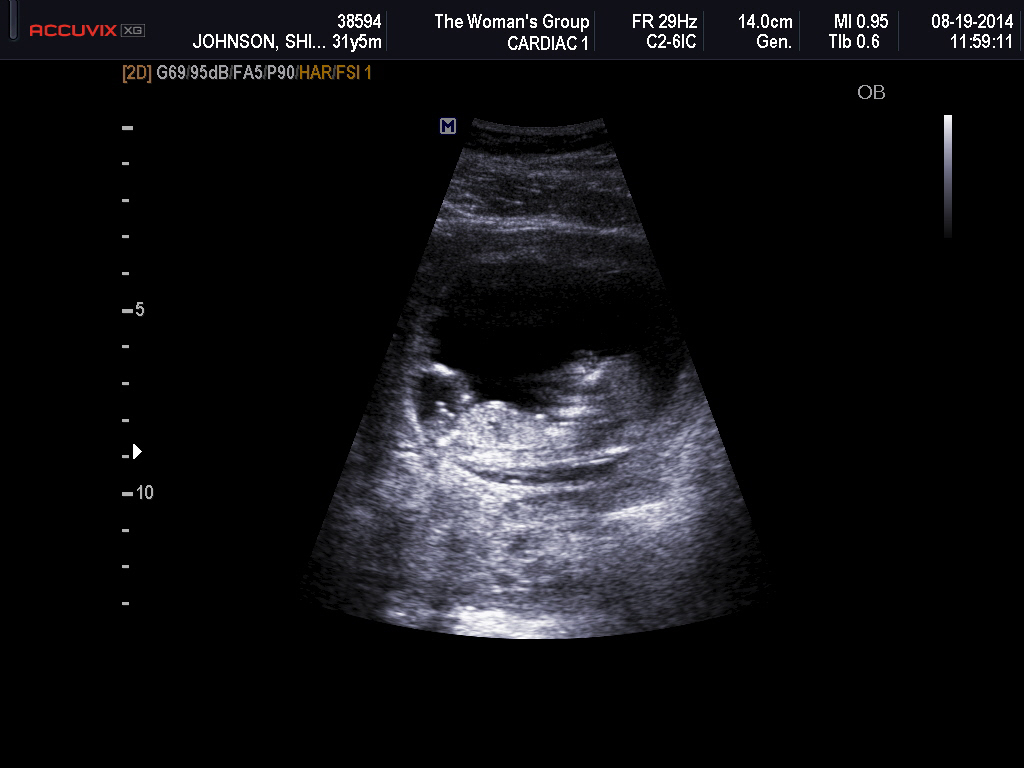

Hi ladies. We just had our first scan and baby was dating a bit ahead at 12w6d. Would love any guesses at gender :-) I have my theories, but am hoping for confirmation!! Thank you in advance!!